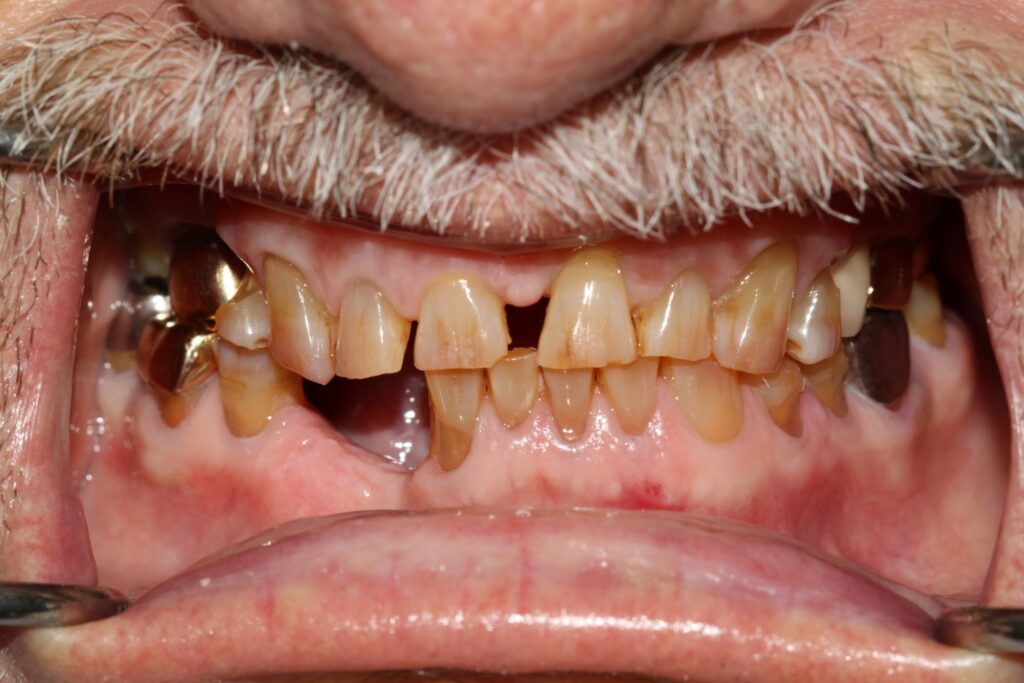

Prosthodontics (also known as dental prosthetics or prosthetic dentistry) is one of the nine dental specialties recognized by the American Dental Association (ADA). Prosthodontists specialize in the diagnosis, restoration, and replacement of missing teeth.

Extensive training and experience give prosthodontists a unique understanding of restoring the dynamics of a smile and healthy mouth with the creation of tooth prostheses. Becoming a prosthodontist requires an additional three years of specialty training after obtaining a DMD (Doctor of Dental Medicine) or DDS (Doctor of Dental Surgery) degree.